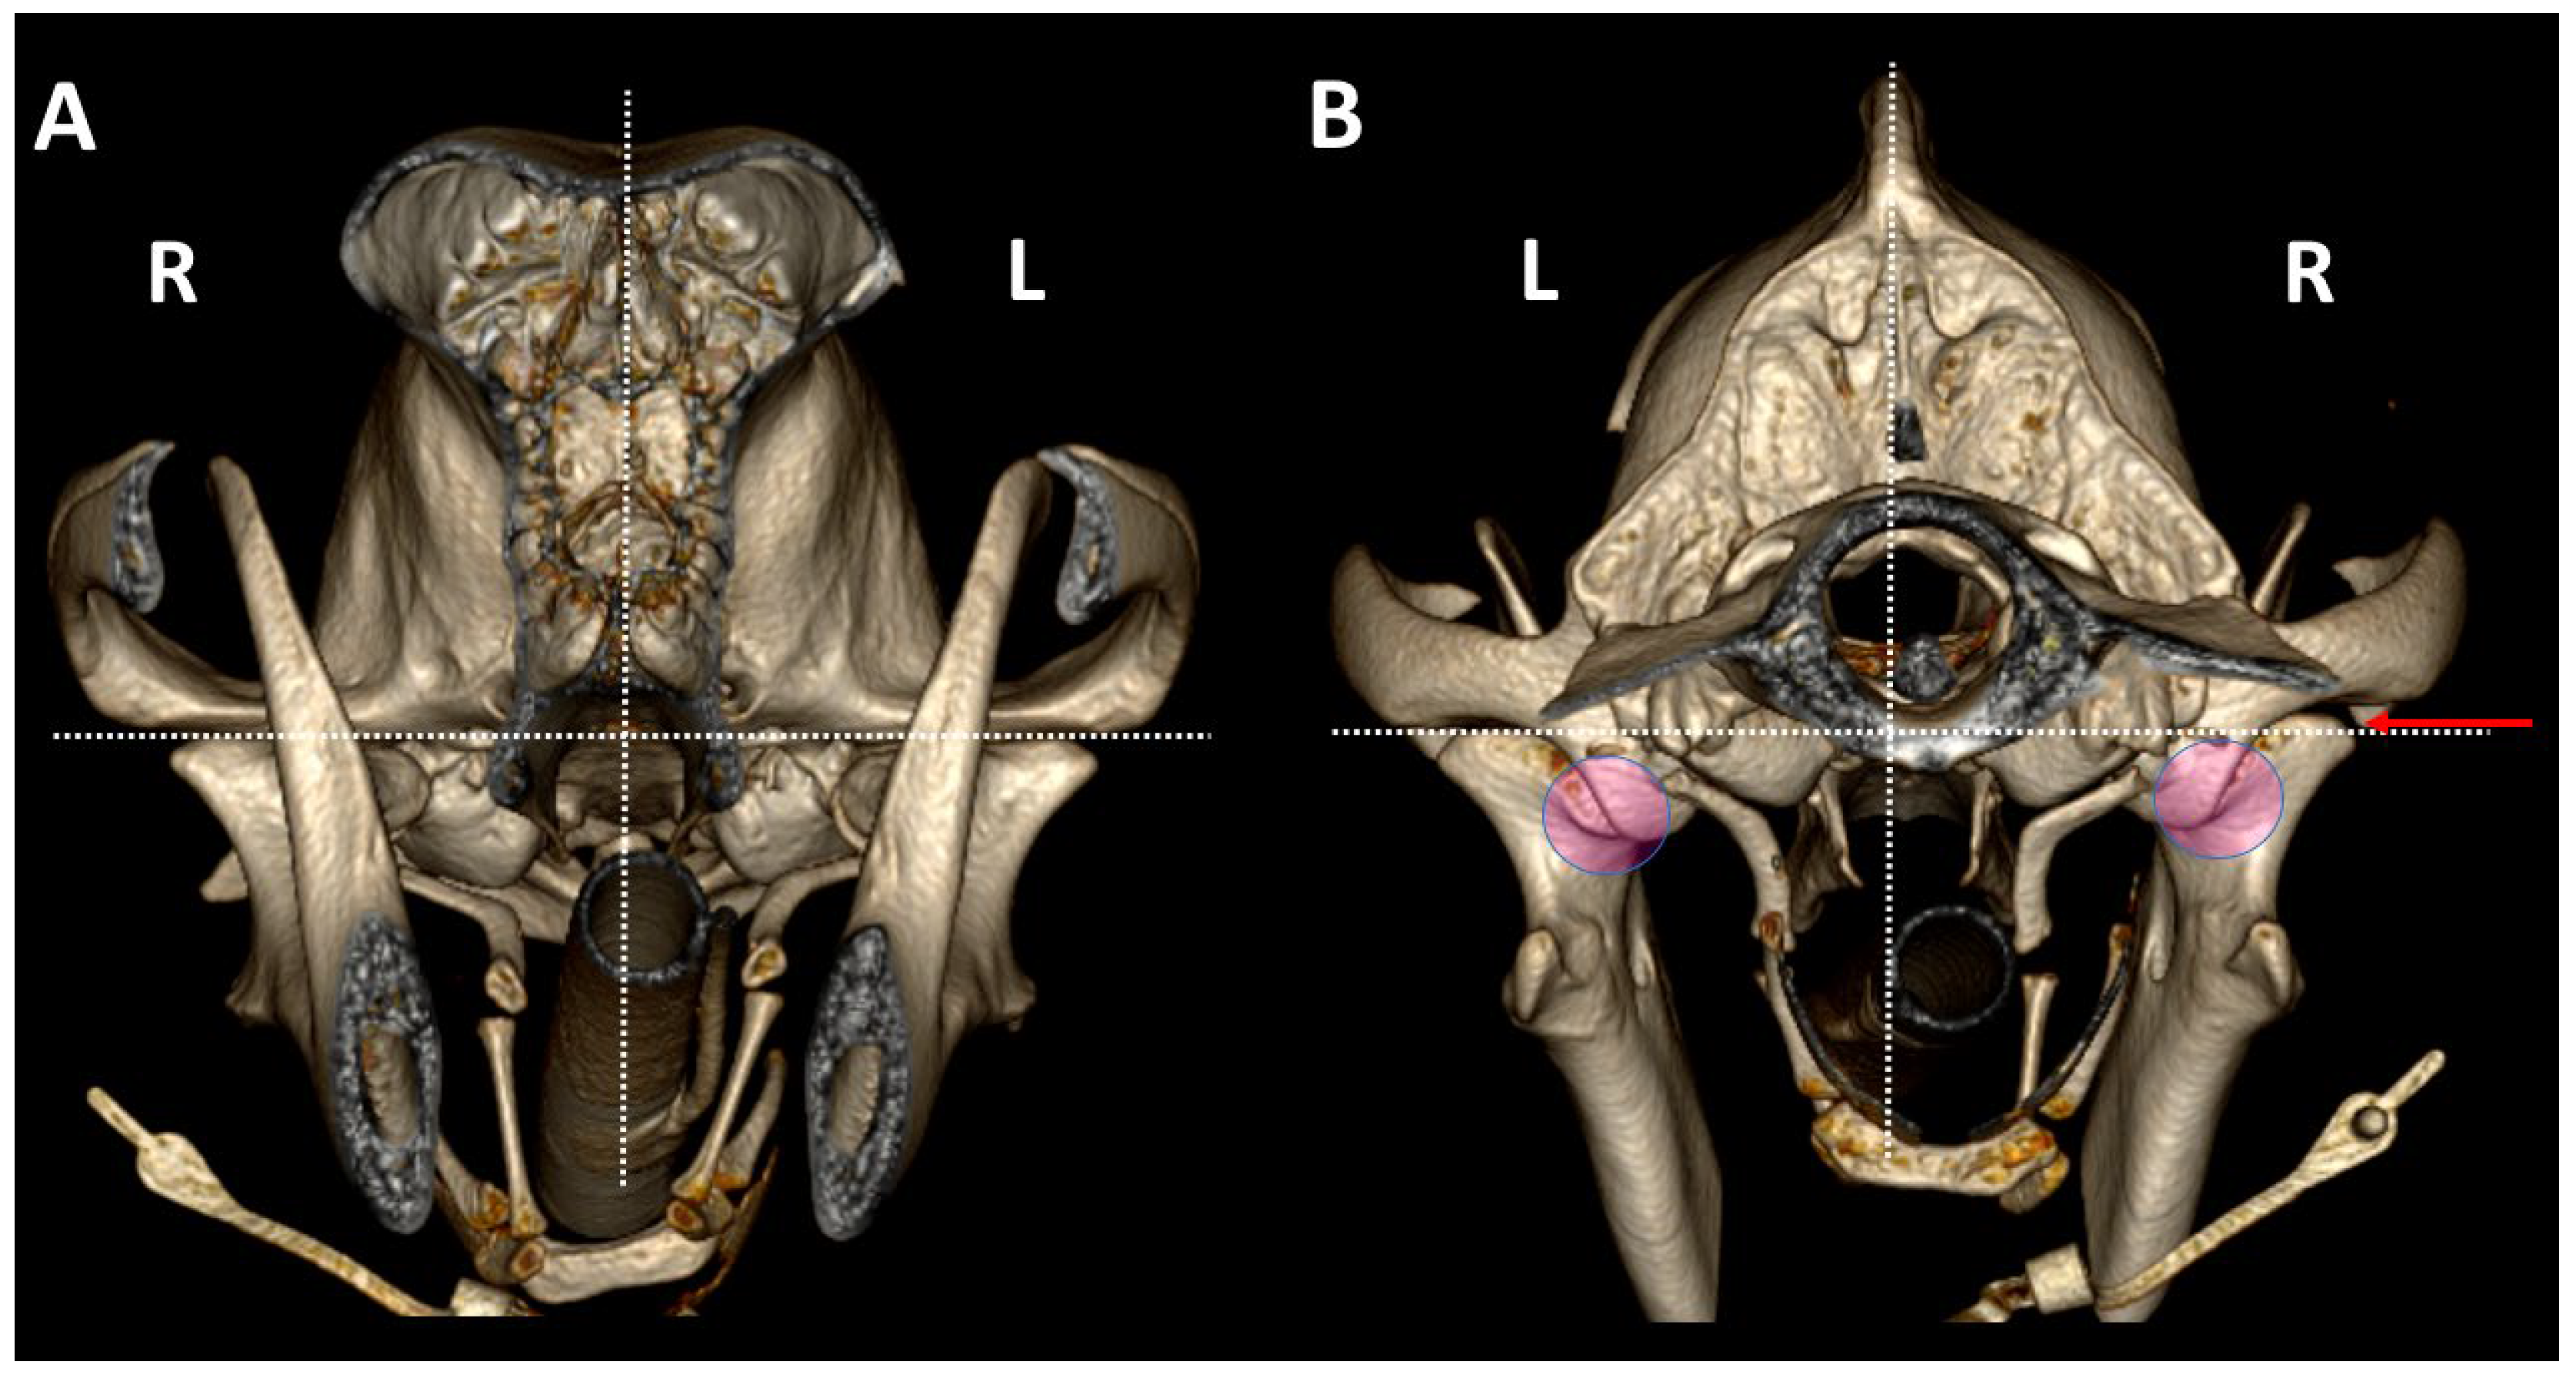

3.2. Comparison by 3DVR of TMJs in Each Dog, According to Skull Type and Age

3.3. A Detailed Assessment of Each TMJ Comparing 3DVR Images with the Three Standard CT Planes